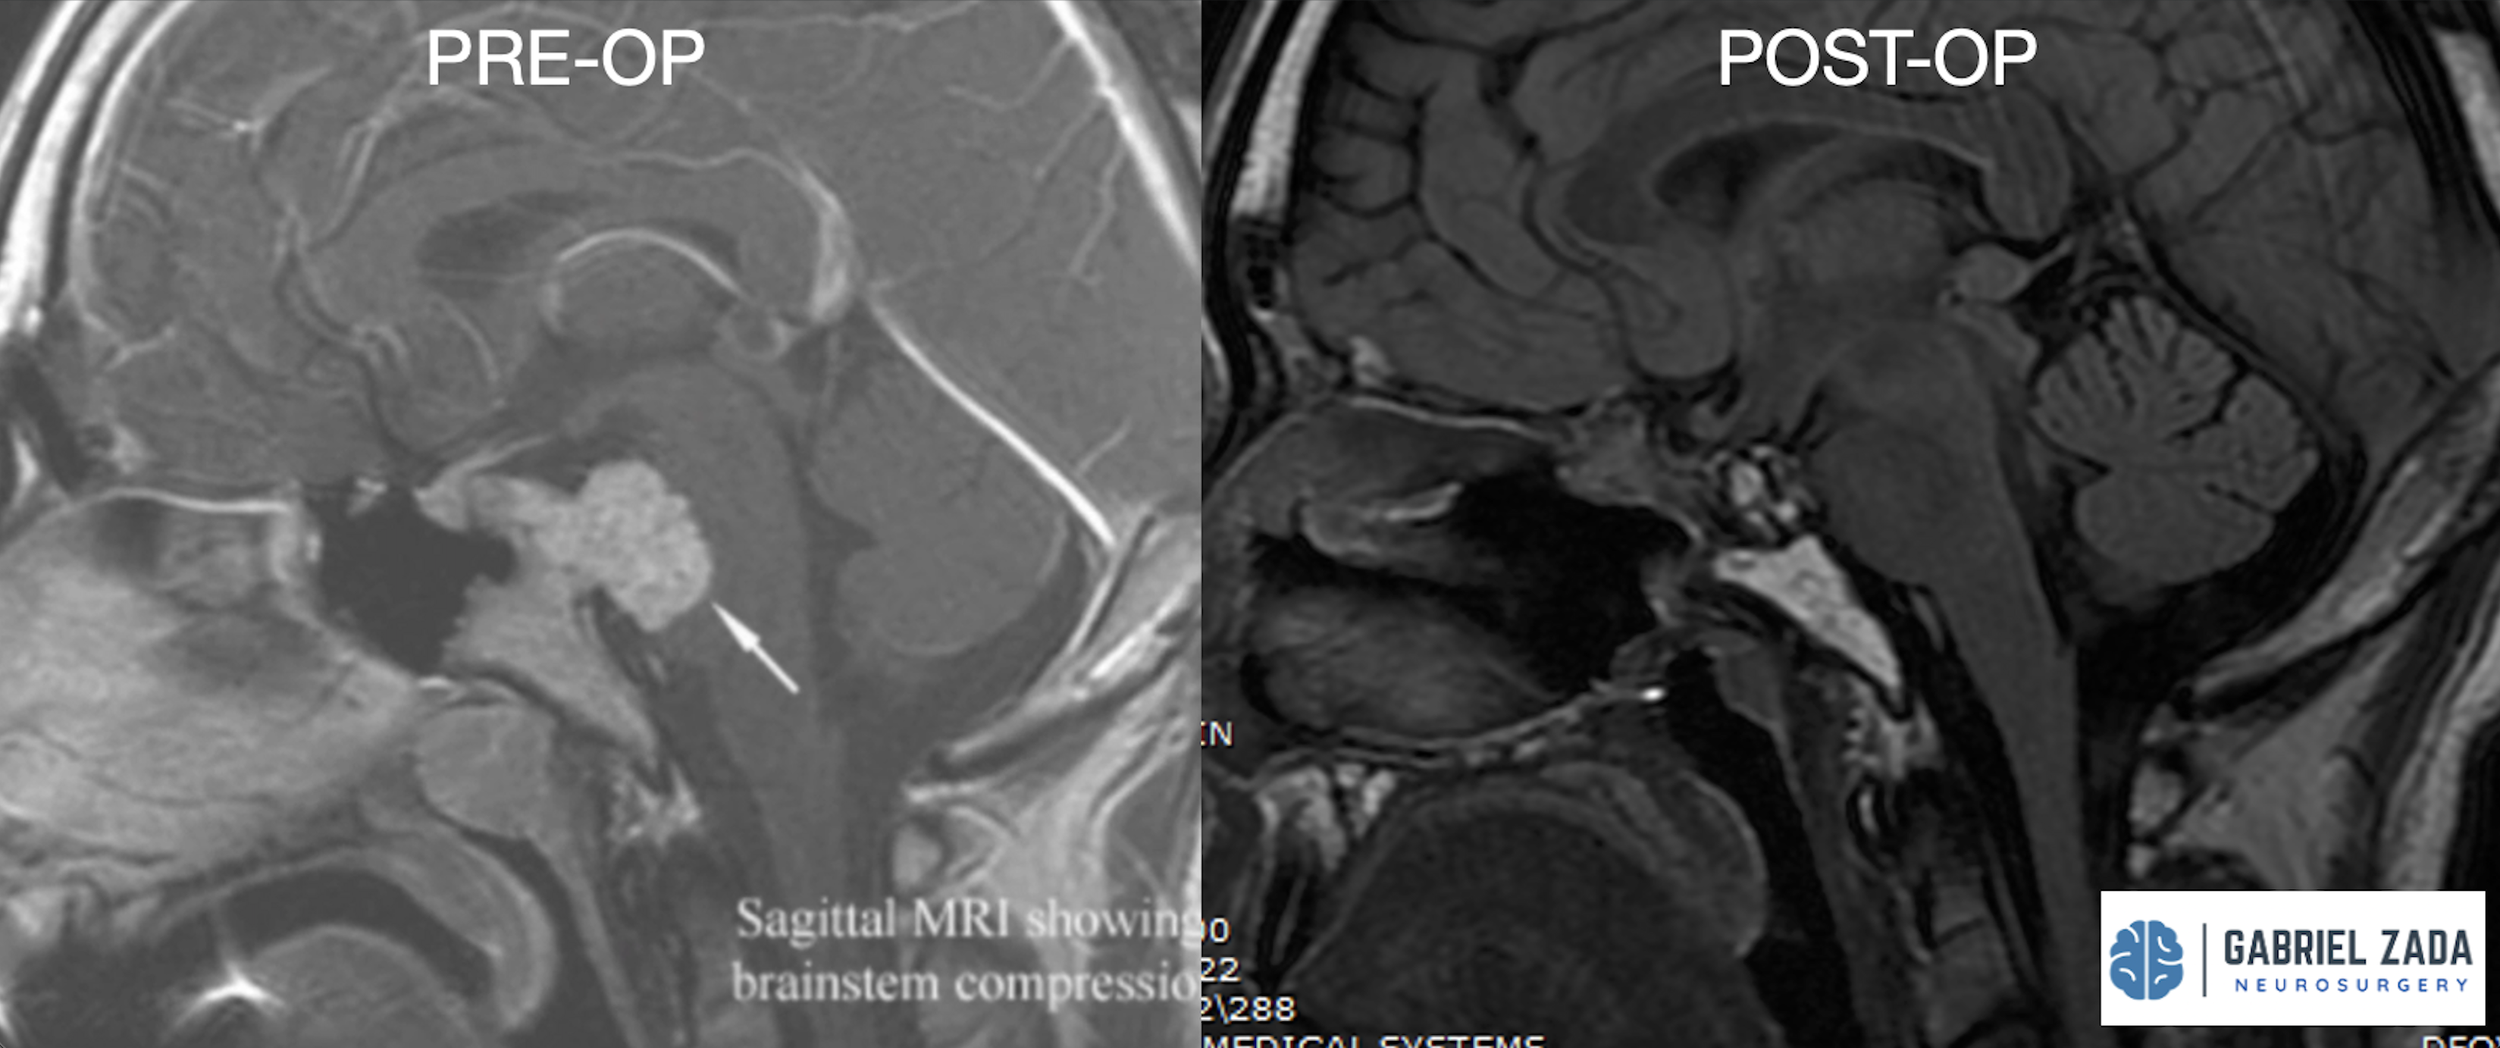

Explore this comprehensive gallery featuring pre‑ and post‑operative imaging of patients with skull‑base tumors treated by Gabriel Zada, MD, MS, FAANS, FACS. These cases highlight Dr. Zada’s expertise in advanced neurosurgical techniques and outcomes.

*Representative cases shown for educational purposes. All images de-identified. Individual results vary.